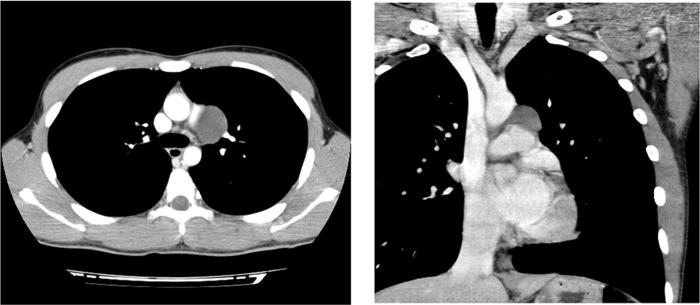

We report a rare case of bronchogenic cyst associated with congenital complete absence of the pericardium. A 17-year-old male was admitted to the hospital for surgical resection of a growing cystic lesion located in the middle mediastinum. The patient was asymptomatic and no significant findings were found on physical examination. Resection of the mediastinal cyst was performed by video-assisted thoracoscopic surgery. The complete absence of the pericardium was immediately observed along with a cystic tumor arising from the mediastinum. After the resection of the cyst, no additional procedure to reconstruct the absence of the left pericardium was performed. Pathological diagnosis was a bronchogenic cyst. Congenital absence of the pericardium may be associated with the bronchogenic cyst and complete absence of the pericardium requires no additional surgical reconstruction, if remaining space in the pleural cavity is small enough to avoid cardiac disposition after surgical resection of the cyst.

摘要

我们报告一例罕见的支气管源性囊肿合并先天性心包完全缺如的病例。一名17岁男性因位于中纵隔的一个逐渐增大的囊性病变入院接受手术切除。患者无症状,体格检查未发现明显异常。通过电视辅助胸腔镜手术切除纵隔囊肿。术中立即观察到心包完全缺如,同时有一个源于纵隔的囊性肿瘤。囊肿切除后,未进行额外的重建左心包缺如的手术。病理诊断为支气管源性囊肿。先天性心包缺如可能与支气管源性囊肿相关,如果胸腔内剩余空间足够小,在手术切除囊肿后能避免心脏移位,那么心包完全缺如无需额外的手术重建。